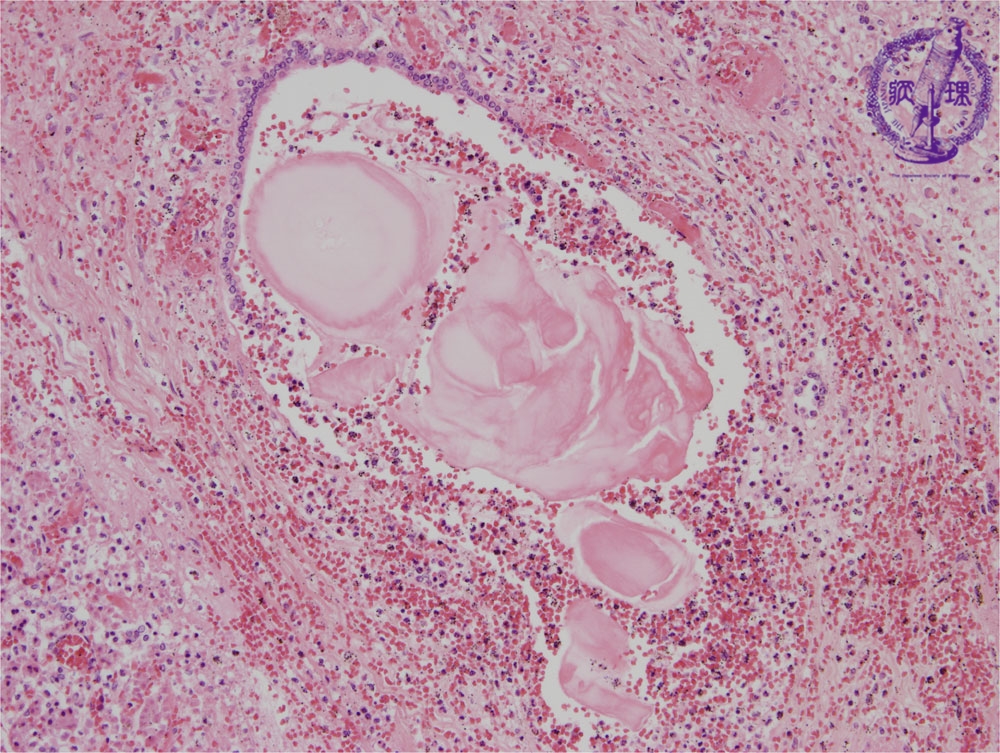

Microscopic image(HE stain, mid-power): There is destruction of the pancreatic duct epithelium and residual pancreatic ducts contain concentrated proteinaceous material. The inflammatory cell infiltrate is composed mainly of neutrophils.